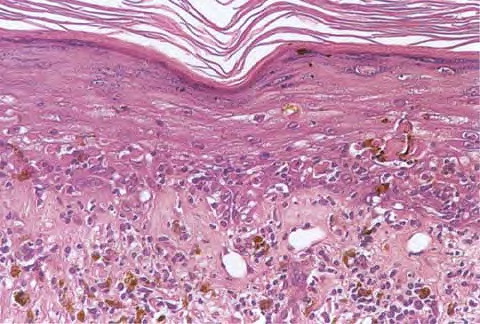

Graft versus Host Disease =داء رفض الطعم للمضيف Graft Versus Host Disease GVHD occurs in situations in which donor immunocompetent T cells transferred into allogenic hosts are incapable of rejecting them. The sources of the T cells include primarily peripheral blood stem cell and bone marrow transplants and, infrequently, unirradiated blood products , solid organ […]